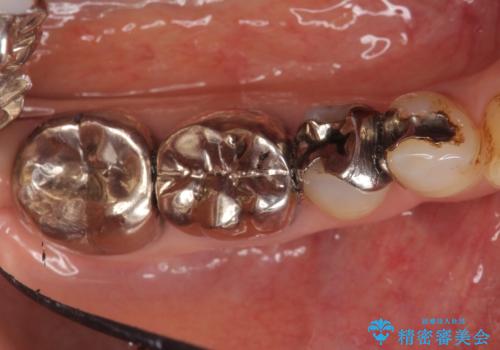

- 右下の古い銀歯のやり替えを希望された方の症例です。

口腔外から見えやすい 4 番目、5 番目の歯はセラミックによる審美的な治療を行い、6 番目、 7 番目の奥歯 2 歯は適合性に優れたPGA(ゴールド)クラウンによる治療を行いました。